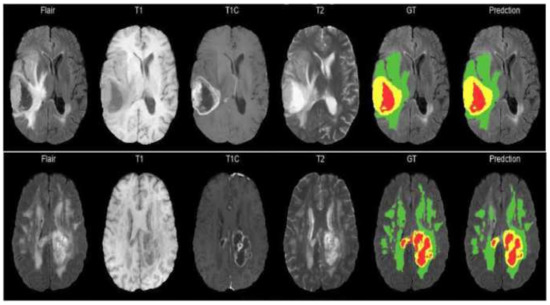

The BraTS 2018 challenge training dataset [22,23,24] consists of 210 HGG and 75 LGG scans. The validation dataset includes 66 different MRI scans. All MRI of the BraTS 2018 dataset has a volume dimension of 240 × 240 × 155. The MRI volumes have been segmented manually by one to four raters, and experienced neuroradiologists approved their annotations. Each tumor was segmented into edema, necrosis, and non-enhancing tumor and active/enhancing tumor. The sample images from the BraTS 2018 dataset are shown in Figure 6.

Figure 6. MRI images and their ground truth for various modalities. Green, red, and blue highlight the ED, NET, and ET areas, respectively.